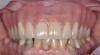

Fig 3. Nonsurgical peri-implant treatment was performed, and the existing prosthesis was modified to enable access for patient-administered oral hygiene.

Figure 3

Fig 4. Four weeks after treatment, the patient presented with healthy peri-implant tissues.

Figure 4